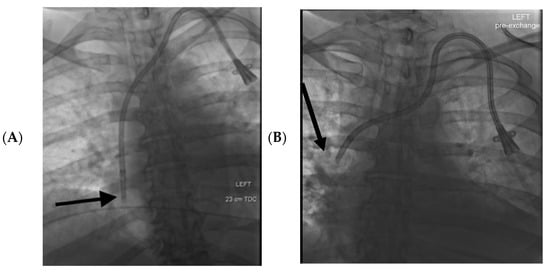

| Mean catheter tip migration | 3.2 cm cranially | 0.8 cm cranially | p = 0.000008 * |

| >2 cm catheter tip cranial migration | 32 (64%) | 26 (20.5%) | Odds ratio for >2 cm of cranial catheter tip migration in left vs. right CVCs Odds ratio: 6.9 95% confidence interval 3.4–14.2 p < 0.0001 |